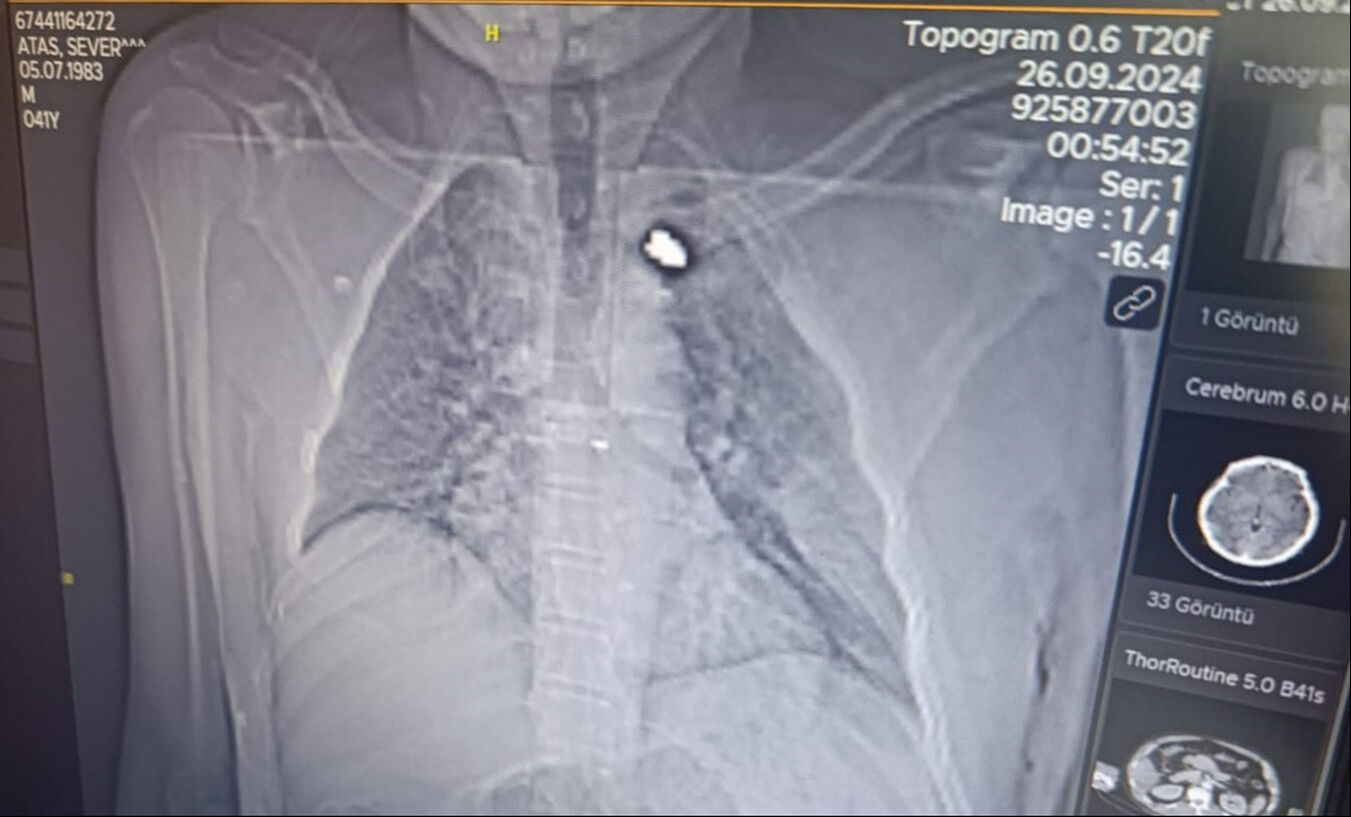

Göğsüne isabet eden mermi ile yaralanan Ataş kanlar içerisinde kaldı. Olayı fark eden yakınlarının ihbarı üzerine Ataş, hastaneye kaldırıldı.

Tedavisi devam eden adama isabet eden kurşunun göğsünde takılı kaldığı görüldü. Polis silahı ateşleyen kişinin tespit edilmesi için çalışma başlattı.